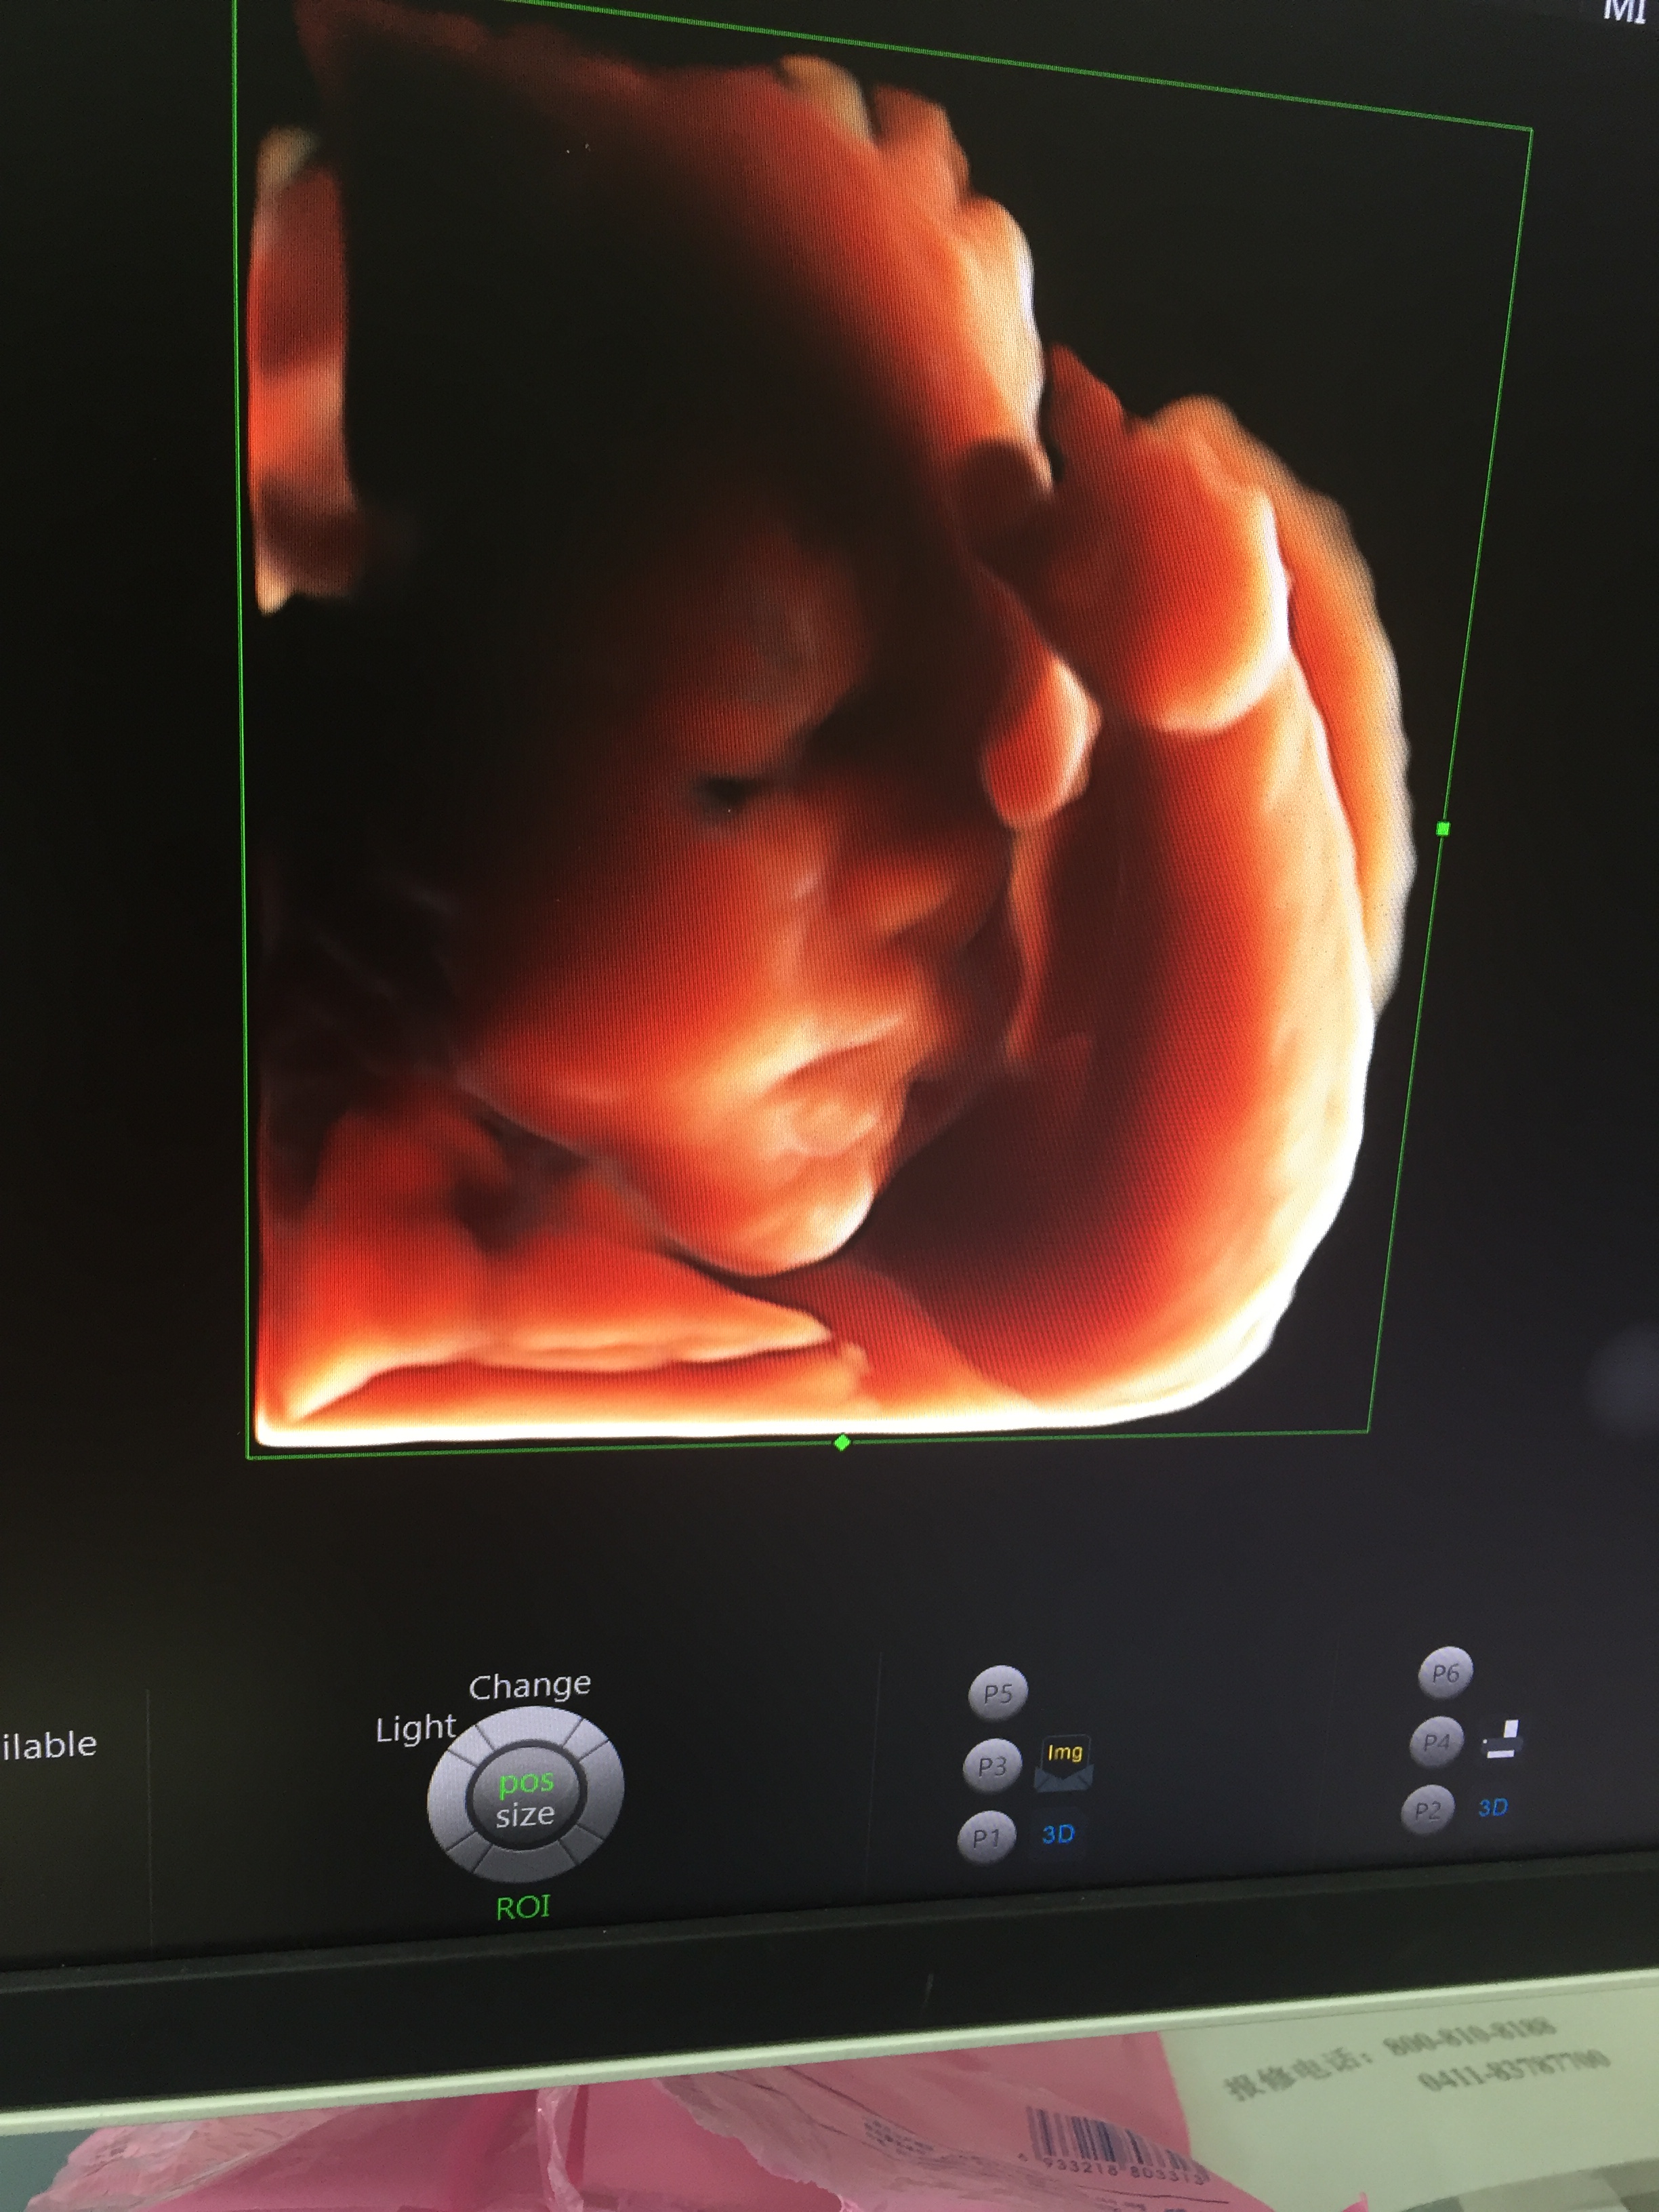

这张照片展示的是我在孕30周时淘淘的样子,这时候他身长约37cm,体重约3斤左右